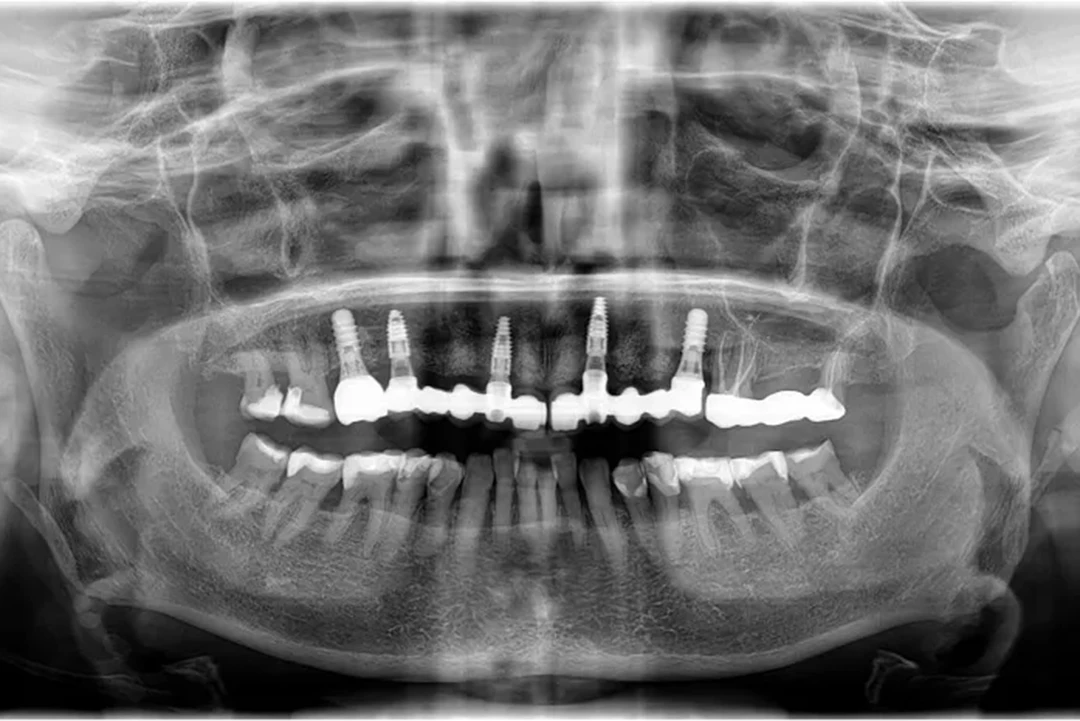

Paciente #2:

De 61 años nos visita con dientes dañados por caries y una prótesis antigua que ya no podía utilizar. Gracias a la planificación digital y la cirugía guiada, realizamos las extracciones y colocamos implantes con una prótesis fija el mismo día. Recuperó su sonrisa y la confianza de inmediato.